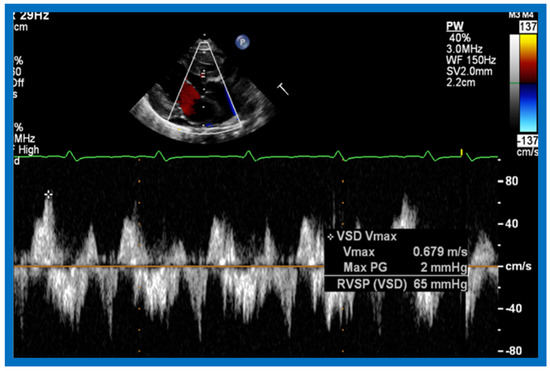

Then, the ventricular septum is evaluated; the ventricular septum is intact in most Type Ia cases. In children with Type I (normally related great arteries), the VSD supplies pulmonary blood flow (Figure 20) while in patients with Type II (transposition the great arteries), the VSD allows blood to flow into the systemic circuit (Figure 21 and Figure 22). In Type I patients, the VSD is demonstrated by 2D (Figure 20A) and the left to-right shunt across it by color (Figure 20B), pulsed and CW (Figure 20C) Doppler signals. Interrogation of the right ventricular outflow tract and pulmonary artery region is performed; peak Doppler flow velocity across the right ventricular outflow tract and pulmonary valve is helpful in identifying obstruction across these sites. The Doppler data from the VSD and RVOT are also helpful in estimating of pulmonary artery pressures. In these Type I babies, the 2D size of the VSD and the peak Doppler flow velocity across it are useful in quantifying the size of the VSD (Figure 20); the higher the VSD Doppler velocity, the smaller the defect. However, in patients with pulmonary hypertension, severe infundibular or valvar pulmonary stenosis, the VSD Doppler velocities do not reflect the size of the VSD. Barring these exceptions, right ventricular and pulmonary arterial pressure may be estimated using modified Bernoulli equation (RV/PA systolic pressure = systolic BP − 4V2).

In Type II patients, the VSD may be small, causing obstruction to blood flow to the systemic circuit; therefore, the size of the VSD should be ascertained by 2D (Figure 21 and Figure 22), color Doppler (Figure 22), pulsed (Figure 25) and CW Doppler, as necessary. In these Type II patients, the high VSD velocity is indicative of subaortic obstruction. Interrogation of left ventricular outflow and PA region may reveal pulmonary or subpulmonary stenosis; the higher the velocity, the more severe the obstruction. Study from suprasternal notch may show aortic coarctation (Figure 26), which is not uncommon in patients with the Type II anatomy.